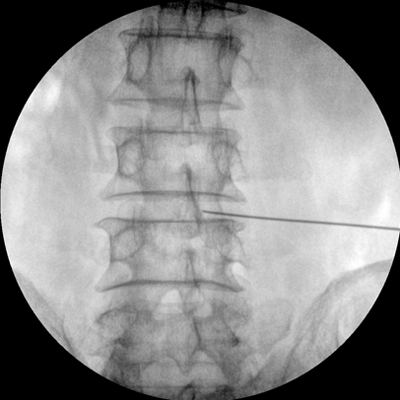

四維電動(dòng)運(yùn)動(dòng)控制,平滑定位,使得復(fù)雜角度快速實(shí)現(xiàn)。

專(zhuān)業(yè)的圖像處理系統(tǒng),為您提供高分辨率、高灰階圖像。